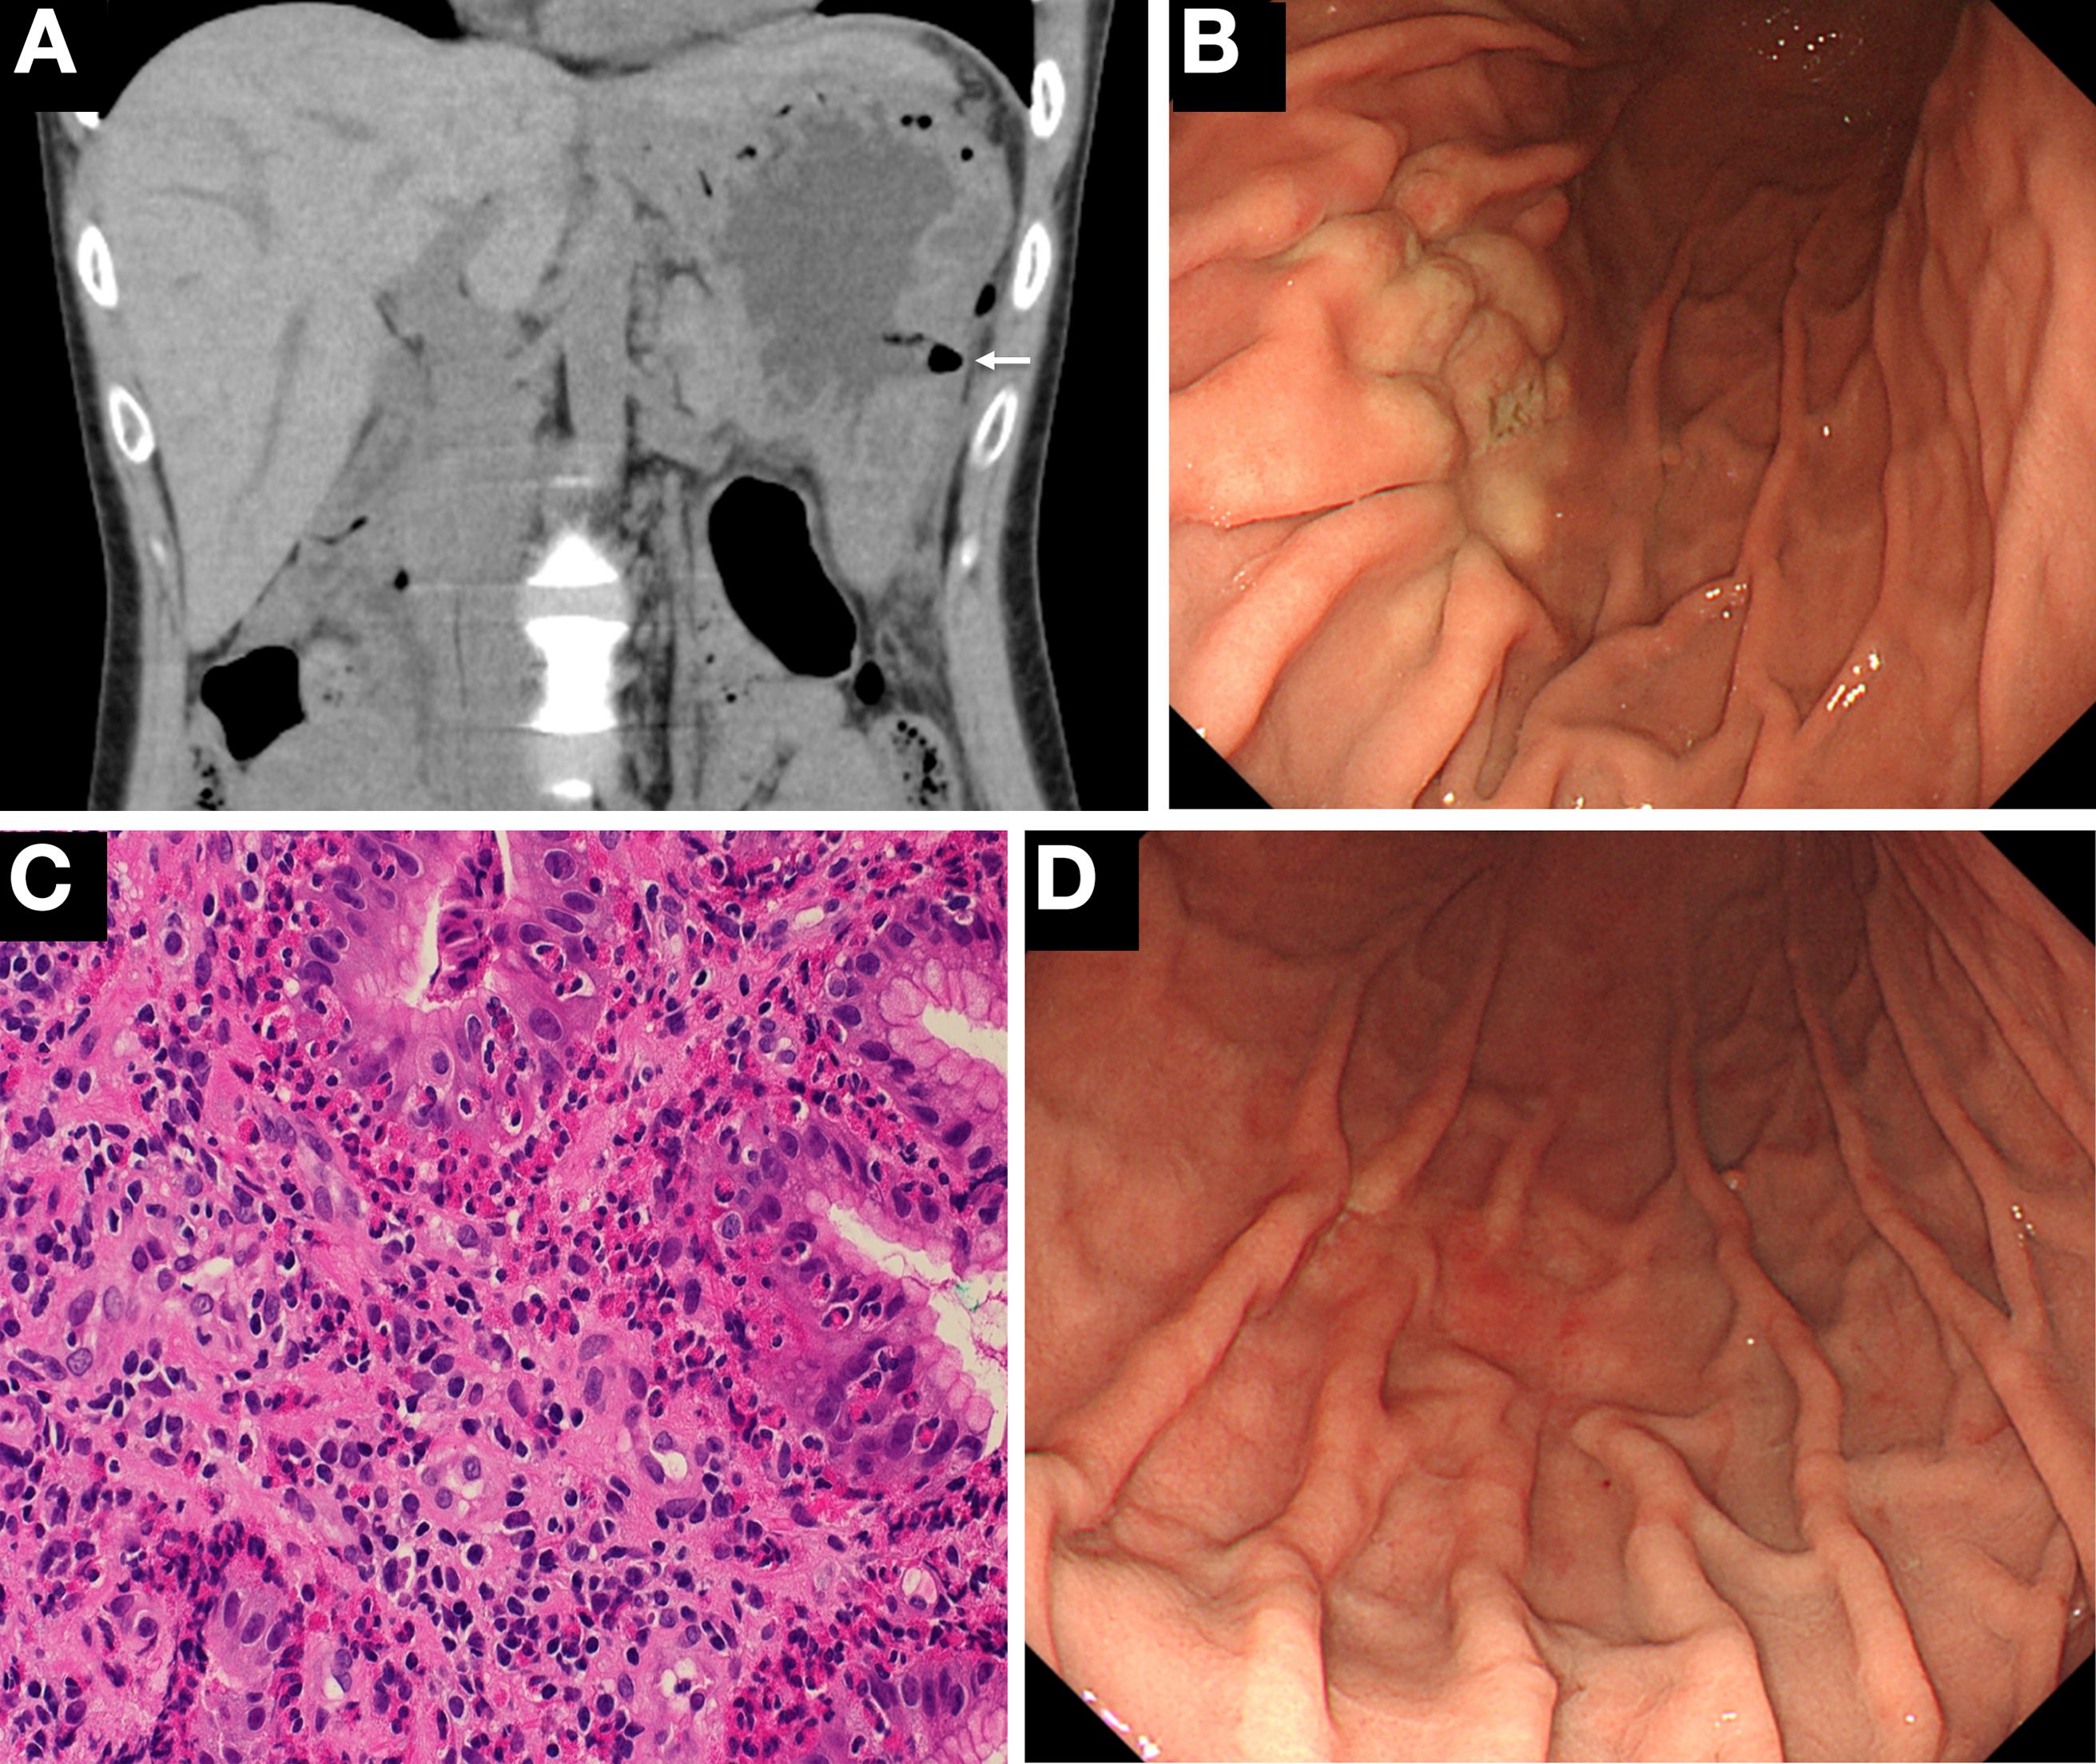

Dua bulan selepas kejadian ini, Lu dimasukkan ke hospital selepas mengadu sakit perut dan sakit belakang yang kritikal sebelum dia disahkan mengalami penyakit penghadaman yang disebut sebagai ‘eosinophilic gastroenteritis’.

Penyakit yang jarang berlaku ini menyebabkan perubahan patologi pada dada, perut, hati dan juga sistem penghadamannya.

Ujian darah juga mendapati, Lu dijangkiti sekurangnya tiga parasit akibat daripada memakan ketam berkenaan.